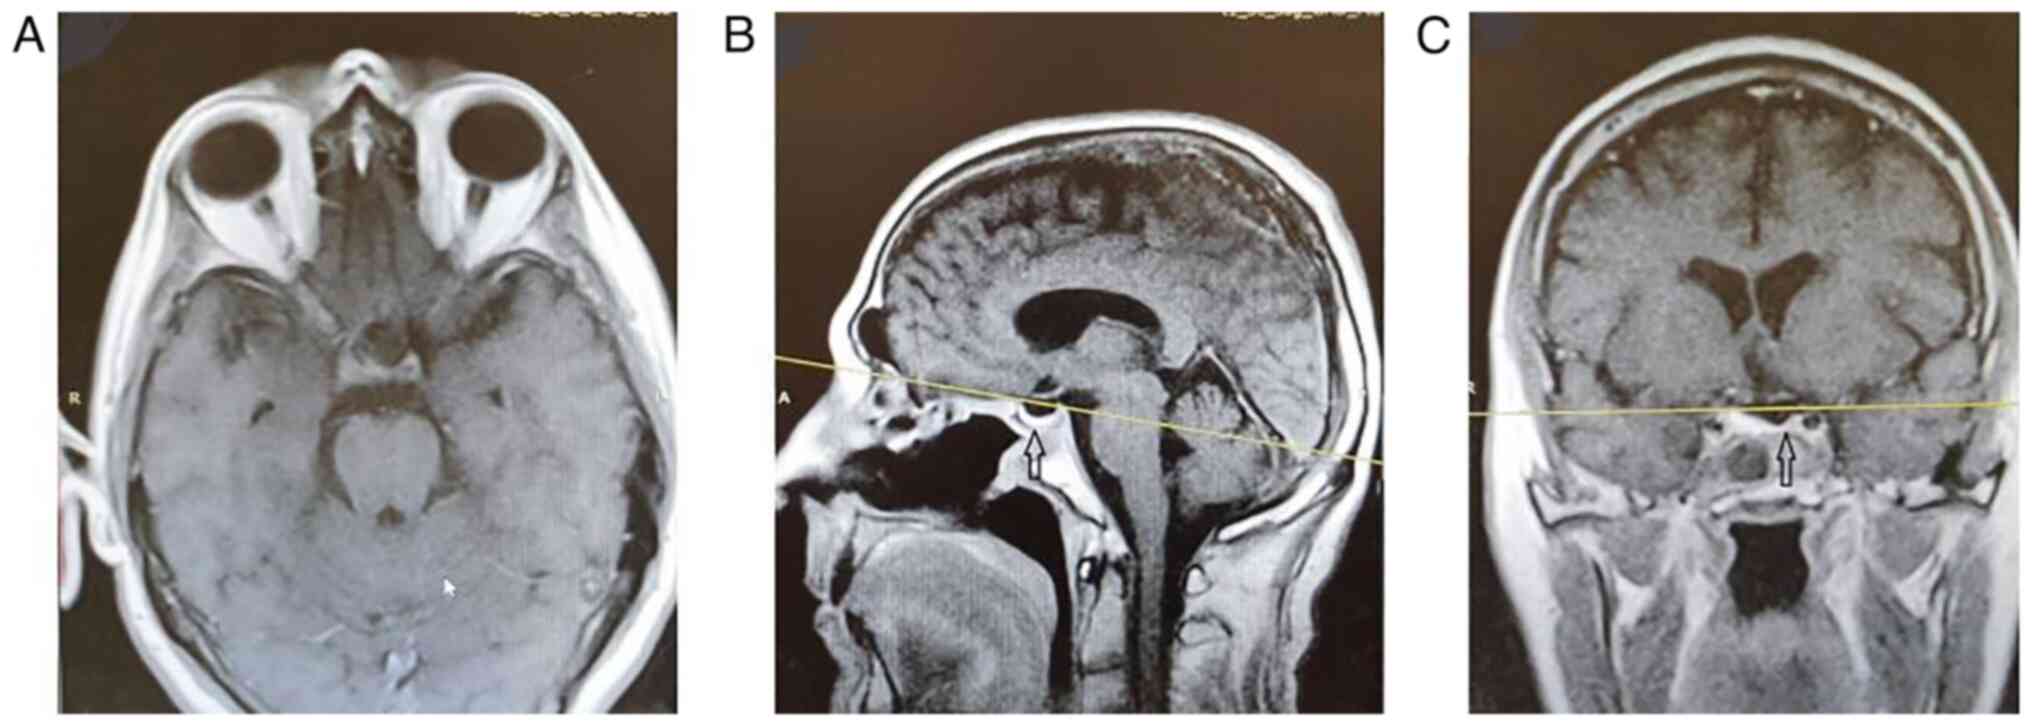

Comparison of the endoscopic endonasal to microscopic sublabial transsphenoidal approach in a case series of pituitary macroadenomas

For a number of years, the microscopic sublabial transsphenoidal (MST) approach was considered the gold standard approach for the treatment of pituitary macroadenomas. Nonetheless, the trend is currently shifting away from the MST to the endonasal transsphenoidal (EET) approach. The aim of the present study was to examine the post‑operative outcomes of the first cases operated by a team of two young surgeons using the EET approach, compared to the cases operated by a team of senior neurosurgeons with extensive experience with the MST approach. For this purpose, data from 20 patients with pituitary adenoma were retrospectively collected from a single center who were operated by the current and previous pituitary‑surgery teams. All the patients who presented with visual impairment in the EET group recovered completely (5/5), whereas 4/5 patients in the MST group recovered completely. Primary hospitalization duration was similar in the two groups. Gross tumor removal was achieved in 90% of patients in the EET group compared to 70% of the patients operated with the MST technique. Intraoperative complications were comparable between the two groups. The first cases operated at the center with EET proved to have better visual outcomes and a larger tumor removal when compared to the MST group. A greater experience in using this technique could exponentiate the differences in the post‑operative outcomes, such as a lower hospitalization duration and fewer intraoperative complications. On the whole, colleagues who have yet to familiarize themselves with the EET approach could perhaps be encouraged to learn to utilize this technique, provided that their center is staffed with an experienced team of skull base surgeons to intervene in an intraoperative complication.

Figure 1